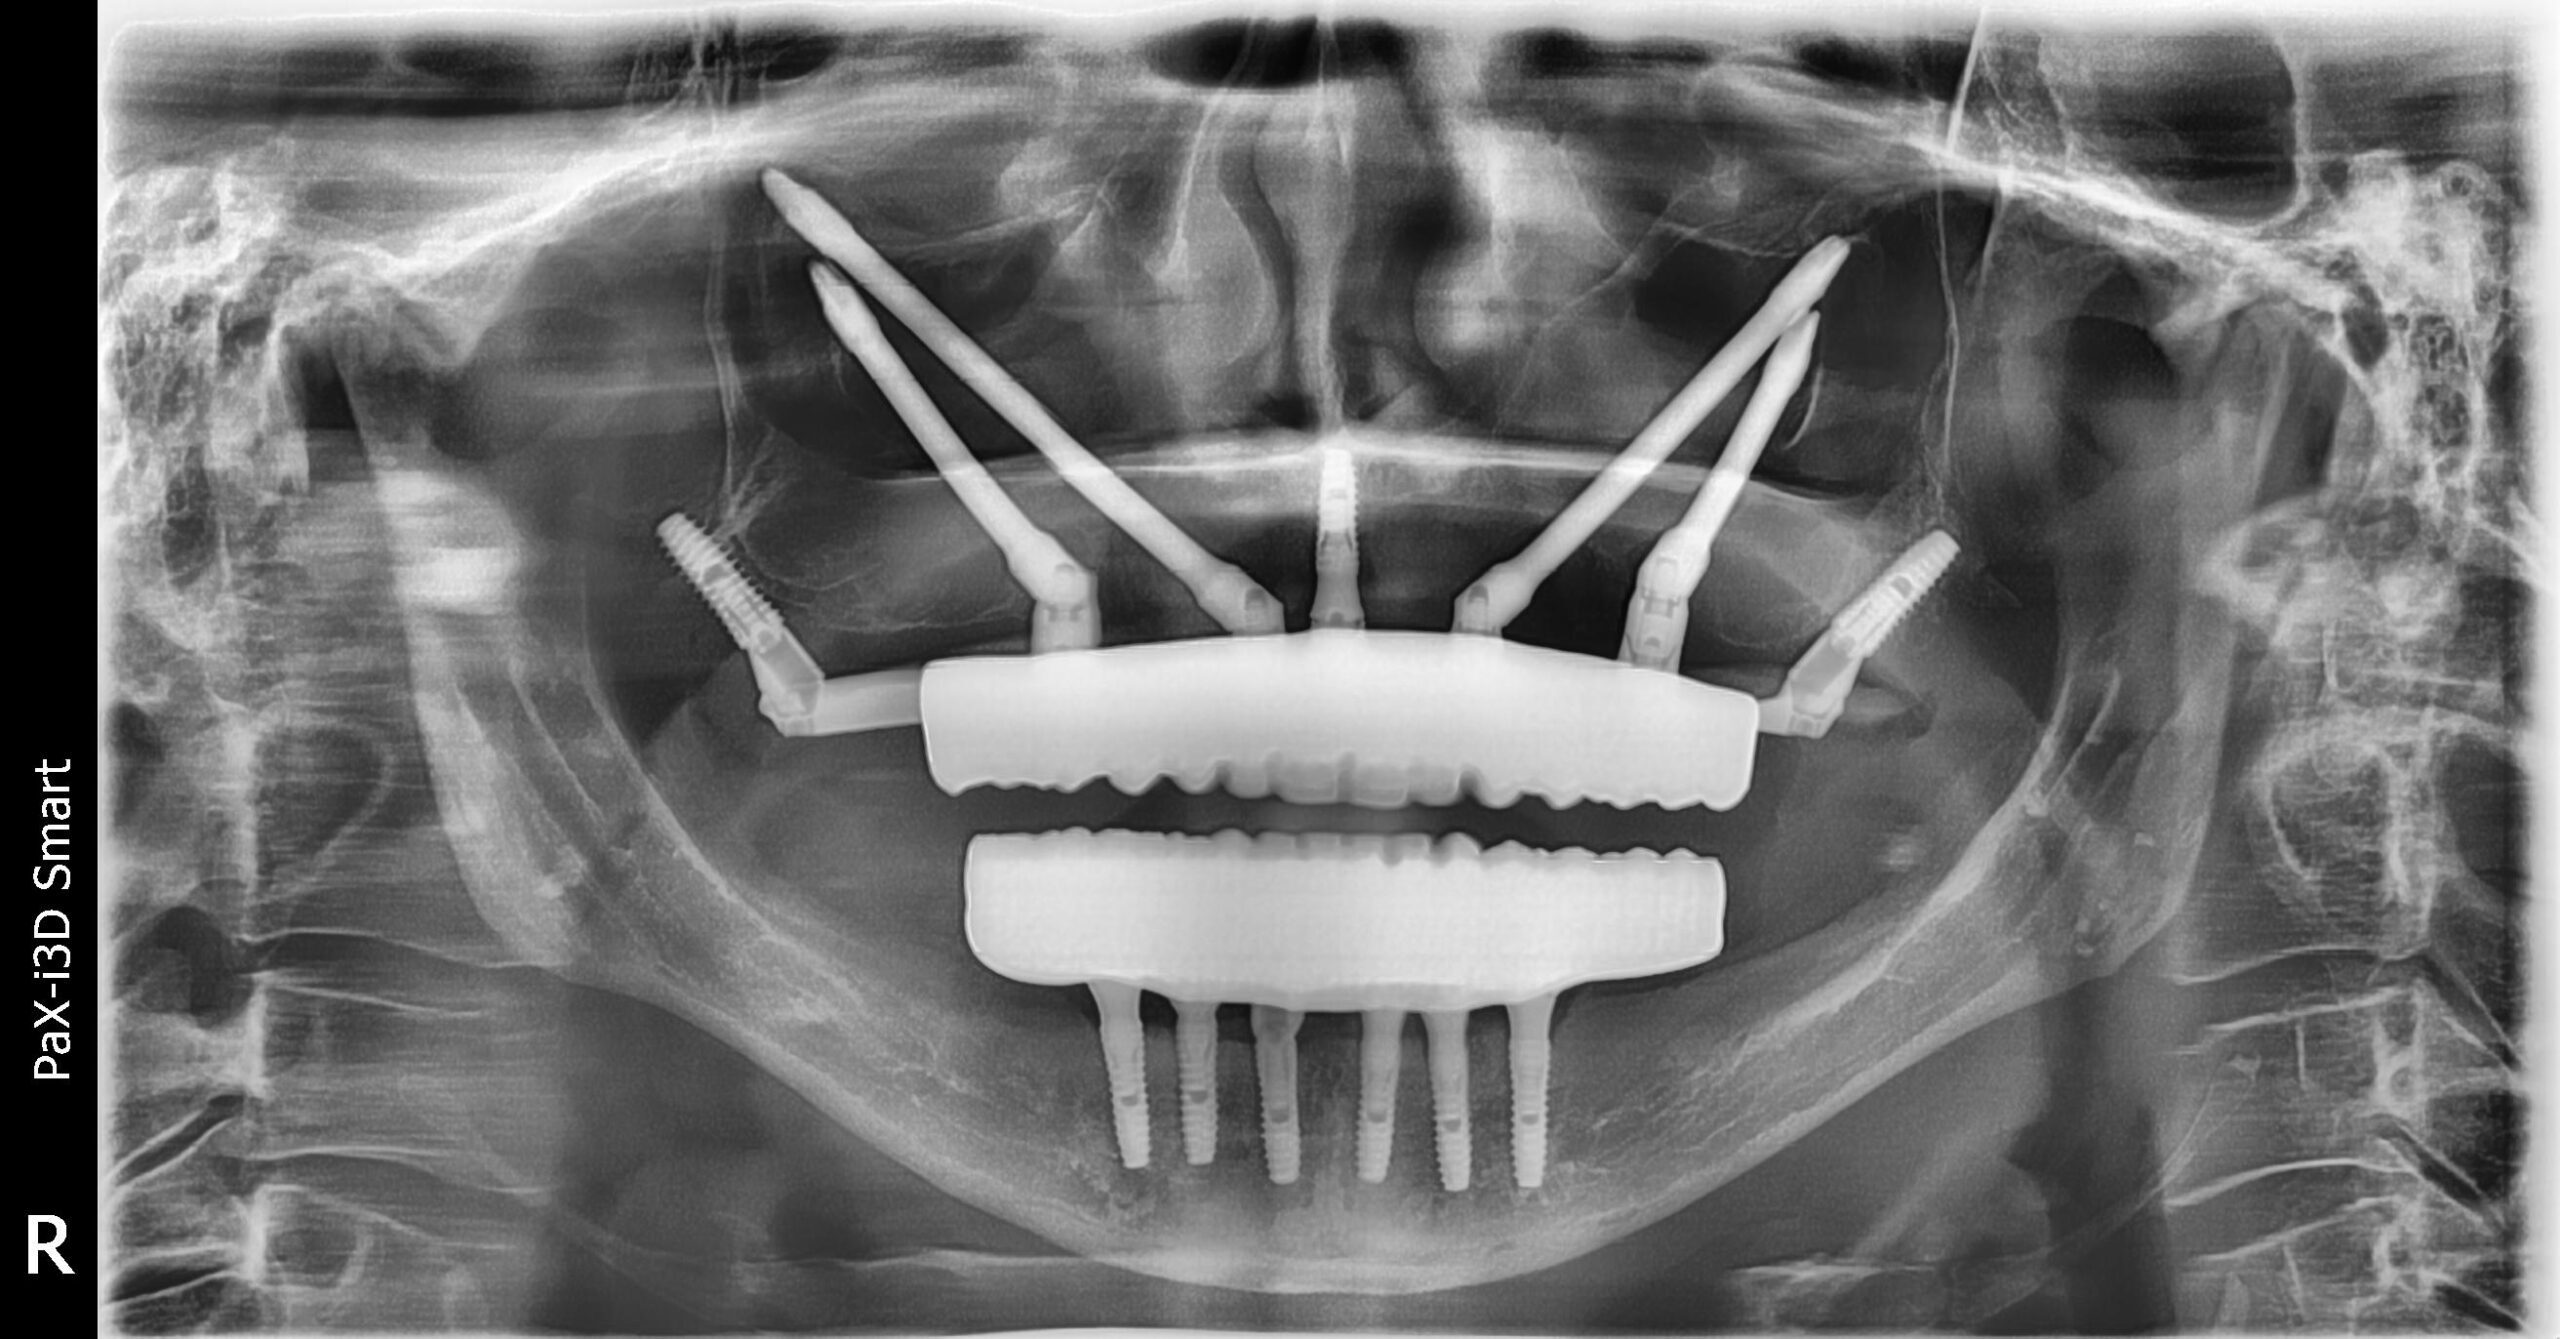

María Paz llevaba muchos años con una prótesis completa superior y pocas piezas en la parte inferior. El paso del tiempo provocó una gran pérdida ósea, lo que dificultaba la colocación de implantes convencionales. Durante años sufrió una masticación deficiente y las incomodidades de una prótesis removible. Con un tratamiento avanzado, volvió a disfrutar de la comodidad y la seguridad al sonreír.

1. Ausencia total de piezas en el maxilar superior

2. Atrofia ósea severa

Colocación de implantes cigomáticos

Prótesis fija de cerámica en el maxilar superior

Implantes en el maxilar inferior con injerto de encía

Prótesis de cerámica y titanio

Una Boca nueva recuperando la oclusion de la paciente y estabilizando su mordida en clase 1. Evitando la patologia articular y devolviendo la funcion y la sonrisa a la paciente